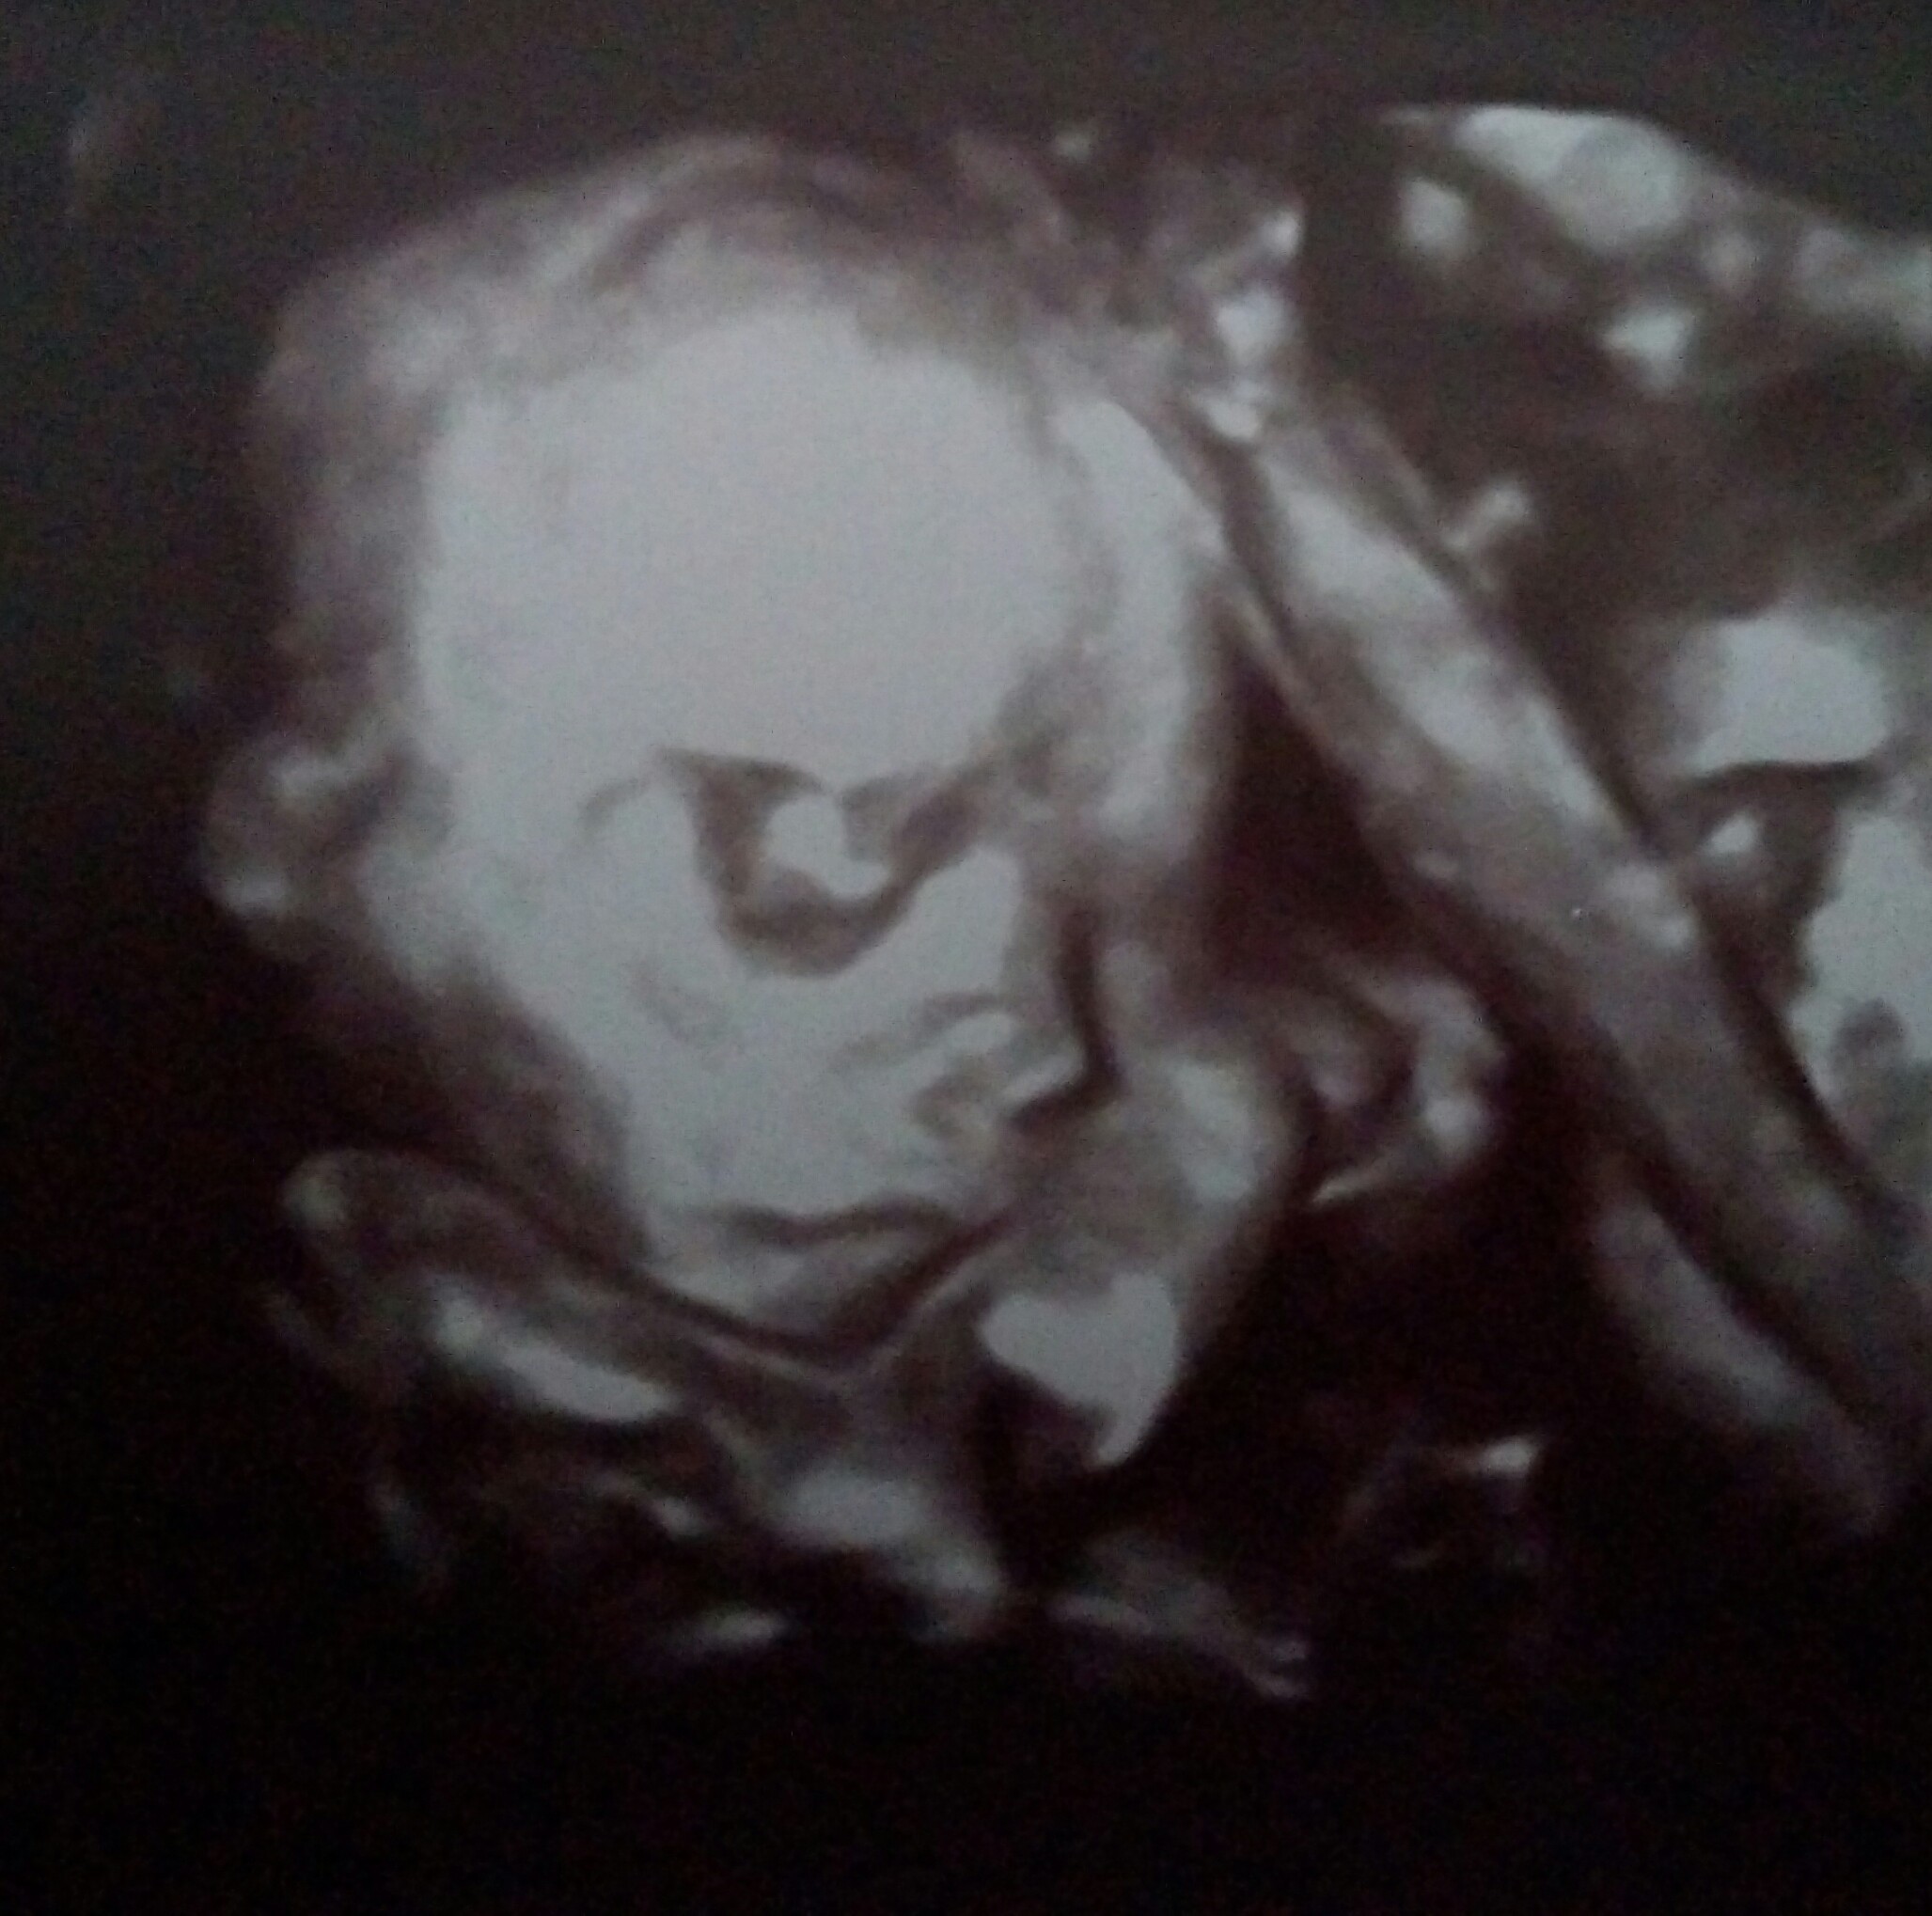

Hej dziewczyny. Nie wiem jak to się stało ale źle się w kalendarz wpisałam bo to połówkowe miałam dzisiaj. Z dzieciakami wszystko ok :-) Rosną jak na drożdżach juz mają po 413 i 427g...

Załączniki

• IMG_20170807_102851~2.jpg

IMG_20170807_102851~2.jpg

479,2 KB · Wyświetleń: 126

• IMG_20170807_102900~2.jpg

IMG_20170807_102900~2.jpg

455,3 KB · Wyświetleń: 118